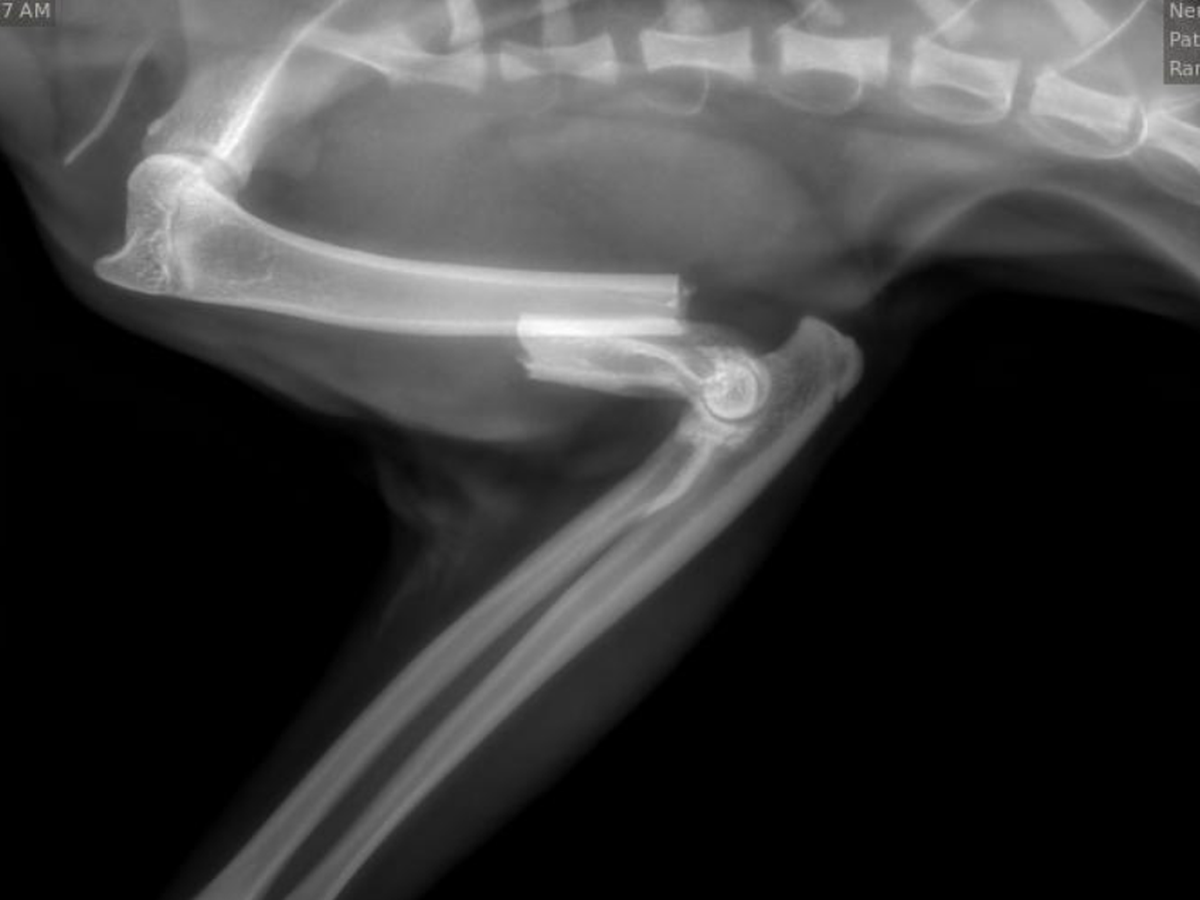

My kitty Benicio broke his arm and needs it to be amputated. He is barely 10 months old and he is the light of my life.

We’ve spent $1700 so far for 1 night at the animal hospital, which does not include the cost of the procedure, and that is $100 less than my monthly fixed income. Please help me keep him with me.